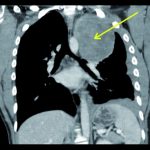

Hier konnte im MRT eine Patelladysplasie und röntgenologisch die klinisch diagnostizierte Patellalateralisation bestätigt werden. Als Nebenbefund zeigte sich in der MRT eine zystisch tumoröse Raumforderung von etwa 2 x 1 x 2 cm im Bereich des distalen Femurs mit der Verdachtsdiagnose: „Gutartiger Knochentumor im Sinne eines Enchondroms“. Die Diagnose wurde durch Röntgenbild, MRT und CT, aber auch sonographisch gesichert.

Die diagnostischen Möglichkeiten zur Klärung des Befundes und prognostischen Aussagen sind vielfältig. Zeigt sich im Röntgenbild und CT der stammnahen Enchondrome eine mehr oder weniger zentrale, metaphysär gelegene zystische Struktur mit einzelnen Aussparungen, sind sie in der Regel scharf konturiert mit deutlichem Sklerosesaum [2, 4, 8]. Fleckförmige Verkalkungen können auftreten. Zusätzlich sind mittels MRT, Angiographie und Szintigraphie die wichtigsten Differentialdiagnosen des Knocheninfarktes und Chondrosarkoms sowie die Dignitätstendenz abgrenzbar [4, 9]. In unserem Fall konnte durch Röntgenbild, MRT und CT, aber auch sonographisch der Befund eindeutig identifiziert und differenziert werden. Gerade die CT-Untersuchung lieferte in unserem Fall keine Hinweise für große Tumoraussparungen mit prognostischer Relevanz für geringes Frakturrisiko.